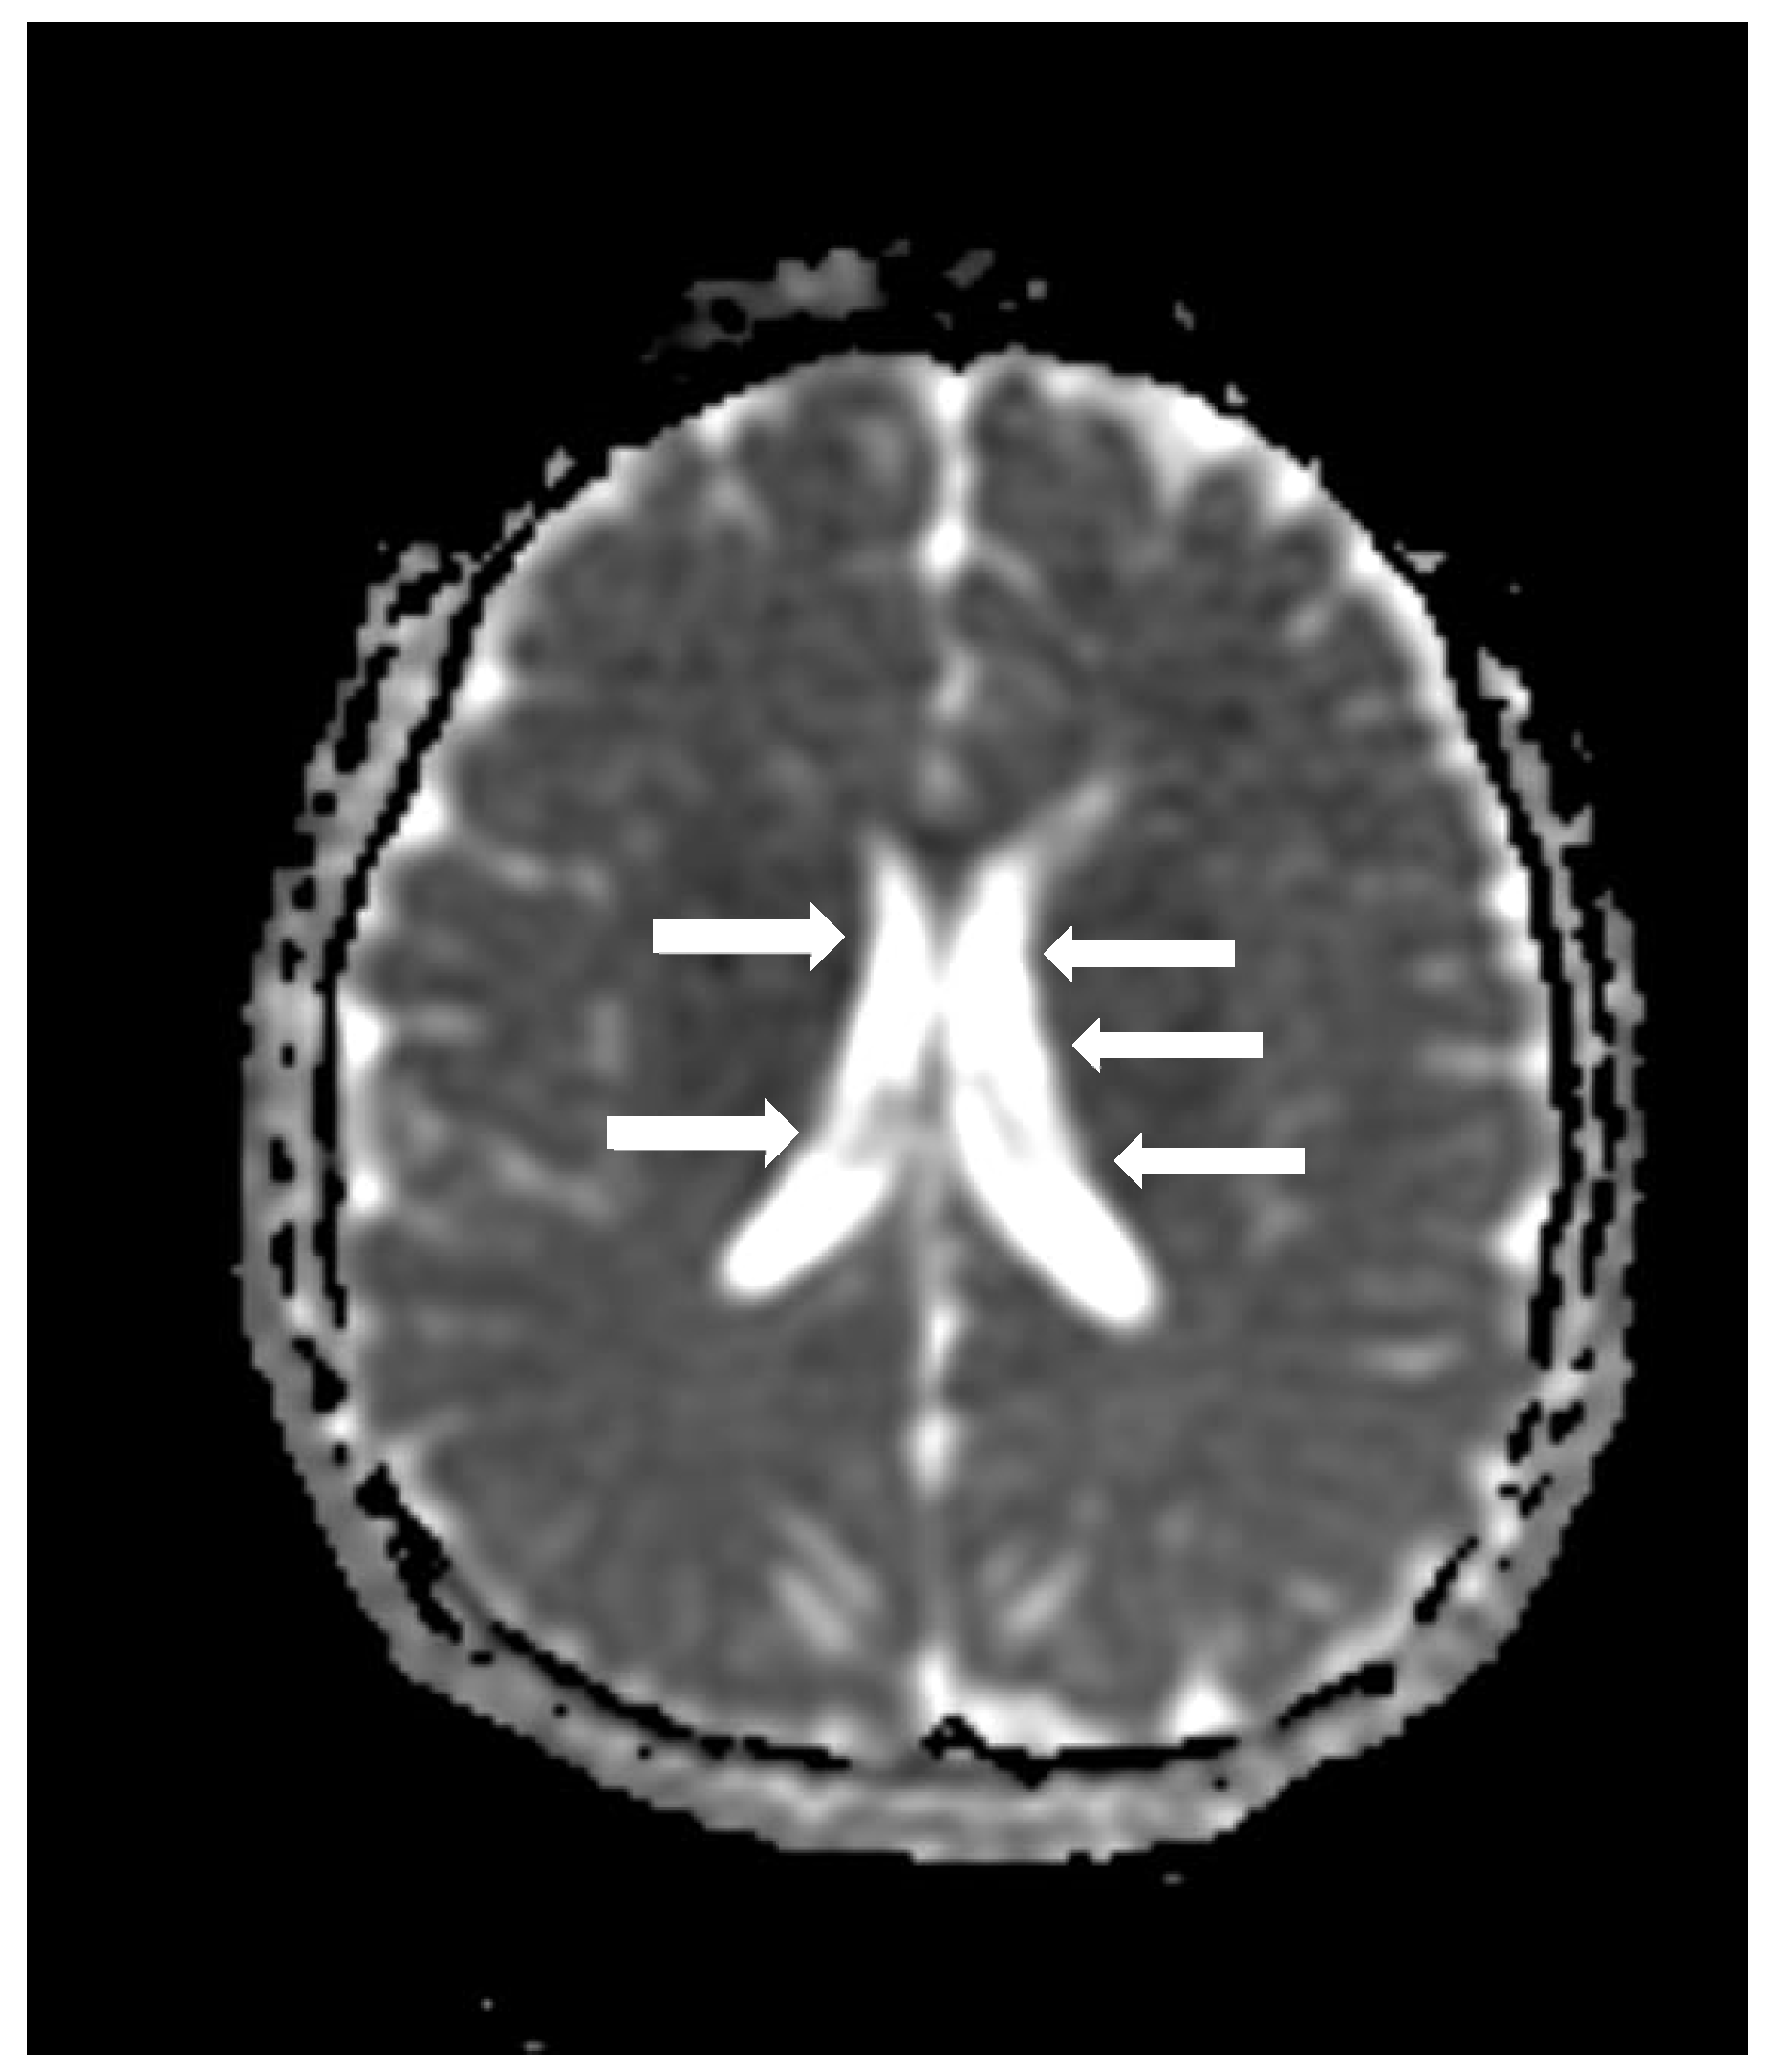

Cranial computed tomography showed a deviated nasal septum with a rightward convexity. Brain magnetic resonance imaging (MRI) with contrast revealed bilateral subependymal periventricular nodular heterotopia (PVNH) at the level of the temporal horns, with no post-contrast enhancement (Figure 3). Additionally, a right choroid plexus cyst was observed in the temporal horn. Audiometry revealed normal bilateral hearing. Neurological examinations showed only mild immaturity in fine motor coordination.

Figure 3.

An axial image of the MRI of the skull showing PVNH in both lateral ventricles. Figure legend: white arrows indicate areas of PVNH, visible as discrete ripples of gray matter adjacent to lateral ventricles.

PVNH, defined as a malformation of cortical development caused by the failure of neurons to migrate to the cerebral cortex, resulting in heterotopic nodules adjacent to the lateral ventricles, is a hallmark feature of MAP1B-related syndromes [20]. LoF variants in MAP1B are also associated with other neurodevelopmental anomalies, such as reduced white matter volume and corpus callosum [2]. However, individuals with MAP1B LoF variants exhibit a wide range of phenotypic variability, with some cases showing normal intelligence and the absence of neurological symptoms [3]. Despite this variability, PVNH appears to be the most consistent neuroanatomical finding [1,2,3].